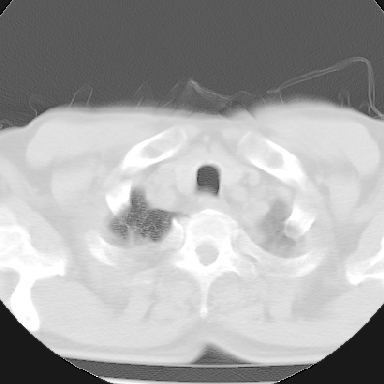

标题: CT8275:M 77 反复咳嗽咳痰10多年,慢性支气管炎请分析 [打印本页]

标题: CT8275:M 77 反复咳嗽咳痰10多年,慢性支气管炎请分析

m 77 反复咳嗽咳痰10多年,再发加重4天

两肺未见明显异常;主动脉弓硬化;左侧冠状动脉硬化?